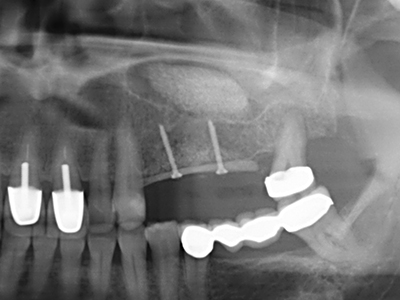

Abb. 15: Die röntgenologische Ein-Jahres-Kontrolle zeigt stabile Verhältnisse des Knochenniveaus.

Abb. 16: Auch intraoral stabile Verhältnisse mit Einbettung der Implantate in keratinisierter Gingiva.